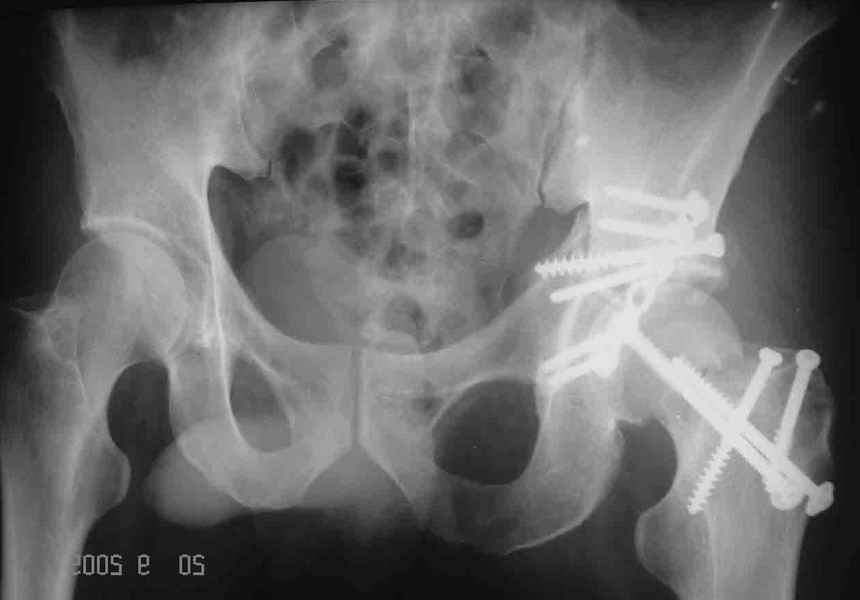

Послеоперационный снимок прямой 5/05/03

|

Послеоперационный снимок боковой 5/06/03

Контрольный снимок перед разрешением нагрузки прямой 13/10/03

Перед разрешением нагрузки боковой 13/10/03

Два месяца нагрузки без костылей 19/12/03

Еще месяц 20/02/04

После протезирования прямой 5/04/04

После протезирования боковой 5/04/04

Больной 18 мая 2003 года в автоаварии получил перелом левой вертлужной впадины, вывих бедра. Госпитализирован в один из стационаров области.Вывих вправлен. В последствии бедро вывихивалось еще дважды. На консультацию был представлен снимок от 19.05.03г., больной переведен к нам 3.06.03г. Снимок при поступлении - перелом впадины, задне-верхний вывих бедра. 05.06.2003 г. выполнено открытое вправление вывиха левого бедра и остеосинтез стенки вертлужной впадины двумя винтами. Послеоперационный период без осложнений. Объем движений в левом тазобедренном суставе восстановился полностью. Выписан на амбулаторное лечение в удовлетворительном состоянии с рекомендациями 3 месяца ходить на костылях без нагрузки на оперированную конечность. На контрольных рентгенограммах левого тазобедренного сустава 13.10.2003 г. - признаки консолидации перелома; плотность, форма головки и состояние суставных поверхностей удовлетворительные. Разрешена дозированная осевая нагрузка, на конечность с использованием дополнительной опоры. 19.12.2003 г. больной обратился с жалобами на боли в левом тазобедренном суставе. На рентгенограммах левого тазобедренного сустава 19.12.2003 г., 20.02.04г. - асептичекий некроз головки бедра. 5.04.04г. - эндопротез. Сейчас ходит без трости, не хромает. Особенность эндопротезирования - при удалении винтов прослежена линия перелома заднего края впадины и предложено установить чашку несколько меньшего диаметра, чтобы она была покрыта несломанной частью.